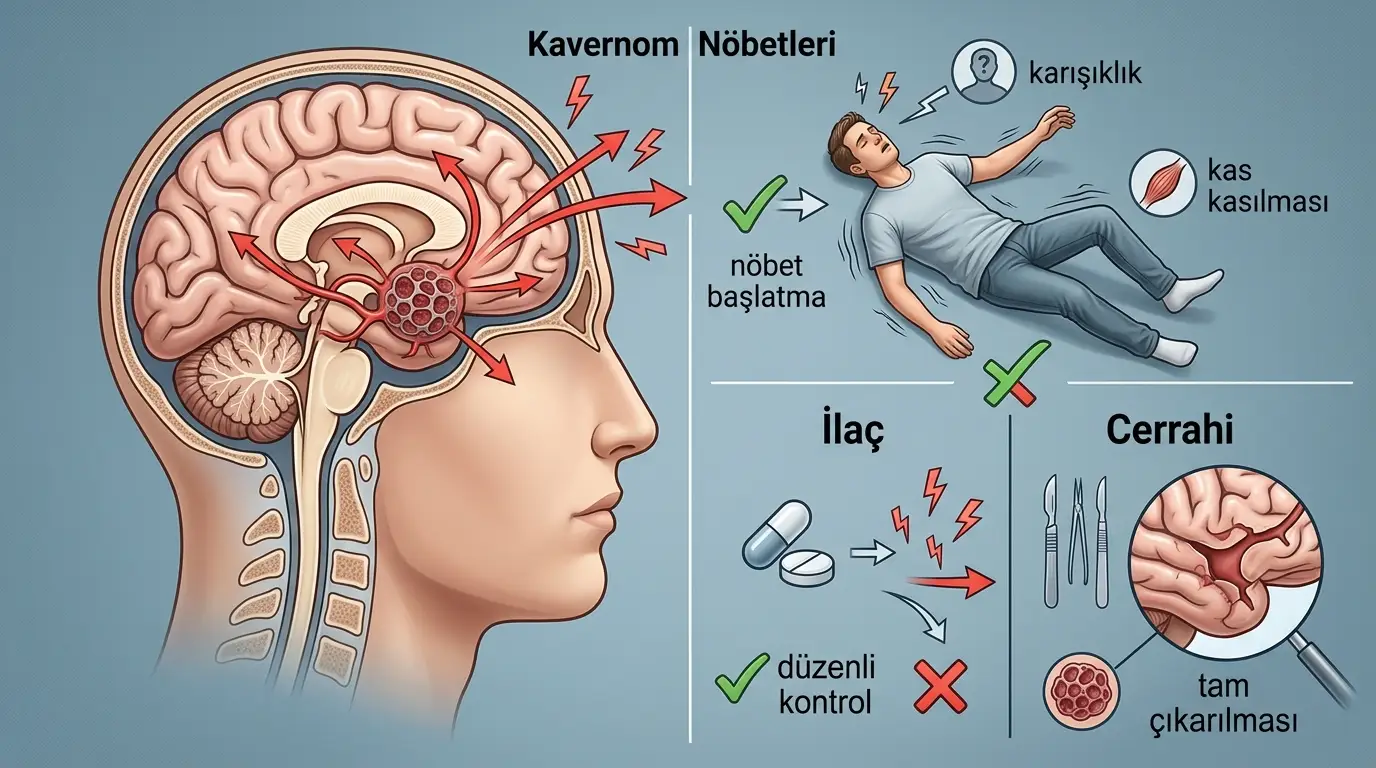

● Kavernom nöbeti, beyindeki anormal damarsal yapıların çevresine sızdırdığı kandan kaynaklanan iritasyon sonucu ortaya çıkan epileptik ataktır; kavernöz malformasyon olarak da bilinen bu yapının tedavi seçenekleri lezyonun konumuna ve kanama öyküsüne göre belirlenir.

● İlaç tedavisi (antiepileptikler) nöbetleri geçici olarak baskılayabilir; ancak kavernomun kendisini ortadan kaldırmaz ve hastaların önemli bir bölümünde uzun vadede yetersiz kalır.

● Cerrahi, özellikle ilaçlara dirençli nöbetlerde birinci tercih tedavi yöntemidir; 45 çalışmayı kapsayan bir meta-analizde cerrahi uygulanan hastalarda nöbet kontrol oranı yüzde 79 olarak bildirilmiştir.

Kavernom nöbeti, beyinde ya da omurilik dokusunda yer alan serebral kavernöz malformasyonun (SKM) çevresine kronik mikrokanama yoluyla hemosiderin — yani demir içerikli kan artığı — biriktirmesi sonucu ortaya çıkan epileptik ataktır. Bu birikinti çevre beyin dokusunu sürekli tahriş eder; anormal elektrik deşarjları oluşur ve nöbet başlar.

Kavernom nöbeti, basit bir uzuvda uyuşma hissinden bilinç kaybının eşlik ettiği tonik-klonik kasılmalara kadar geniş bir yelpazede görünüm sergileyebilir. Kavernomla ilişkili epilepsinin (KİE) görülme sıklığı, supratentoryal yerleşimli lezyonlarda yüzde 23–50 arasında bildirilmektedir.

Yeni başlayan kavernom nöbetlerinde ilk adım çoğunlukla antiepileptik ilaç (AEİ) tedavisidir. Levetirasetam, lamotrijin ve karbamazepin bu grupta sık kullanılan ajanlardır. İlaç tedavisi, nöbet sıklığını ve yoğunluğunu azaltabilir; ancak şu nokta kritik öneme sahiptir: ilaçlar kavernomun kendisini ortadan kaldırmaz, kanama riskini düşürmez ve ileride nöbet yeniden başladığında tedavi süreci başa döner.